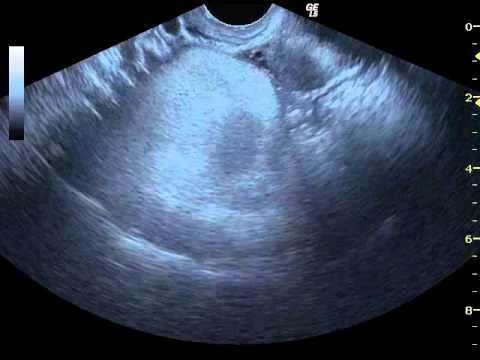

Detaylı Ultrason Nedir: Detaylı ultrason, vücudun iç yapılarını görüntülemek için kullanılan güvenli ve non-invaziv bir tıbbi görüntüleme yöntemidir. Bu prosedür, yüksek frekanslı ses dalgalarının vücuda gönderilmesi ve geri yansıyan dalgaların toplanması prensibine dayanır. Ultrason dalgaları, farklı doku yoğunluklarından farklı şekillerde yansır ve bu yansımalar, cihaz tarafından algılanarak görüntüler oluşturulur. Detaylı ultrason, geleneksel ultrason incelemelerine kıyasla …